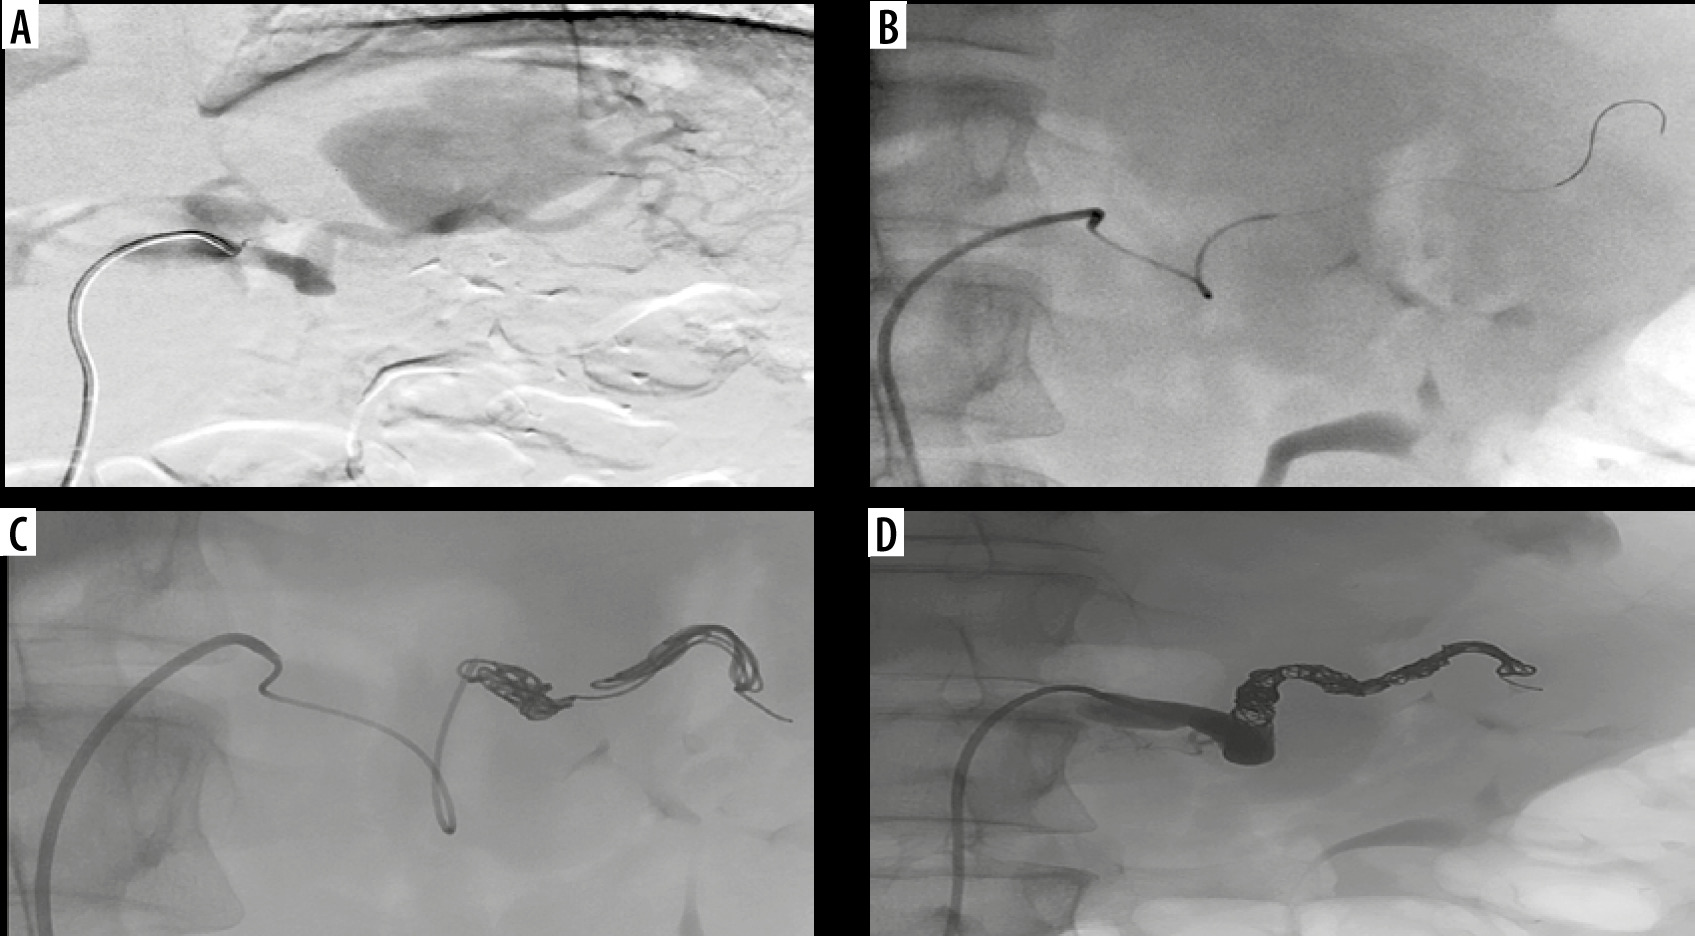

Figure 3

Digital angiography. Selective angiography of splenic artery confirming a giant pseudoaneurysm (A) and selective catheterization, employing a microcatheter, of distal portion of splenic artery (B). Endovascular embolization releasing multiple metallic microcoils into the in-flow and out-flow tracts of the giant pseudoaneurysm (C). Final angiographic control confirming successful endovascular exclusion of the pseudoaneurysm with opacification of the great pancreatic artery (D)